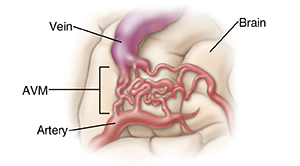

A problem with blood flow

An AVM is a tangle of blood vessels. It can cause pressure to build up in the blood vessel and prevent normal blood flow. If the pressure becomes too great or the wall of the AVM vessel weakens, a blood vessel can burst and blood can leak or spurt into the brain. This can damage parts of the brain that control vital body functions, such as sight, sensation, language, critical thinking, and movements. In some cases, problems caused by an AVM can even lead to death. The high blood flow in an AVM can also shunt the oxygen from the arteries directly to the veins, bypassing the brain capillaries. This shunting can lead to strokes. AVM can be treated based on the type, symptoms, and cause.

| Pressure builds when blood tries to flow through tangled vessels. |